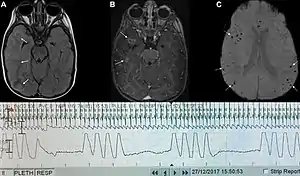

![]() | |

| Graph showing Biot's respiration and other pathological breathing patterns. | |